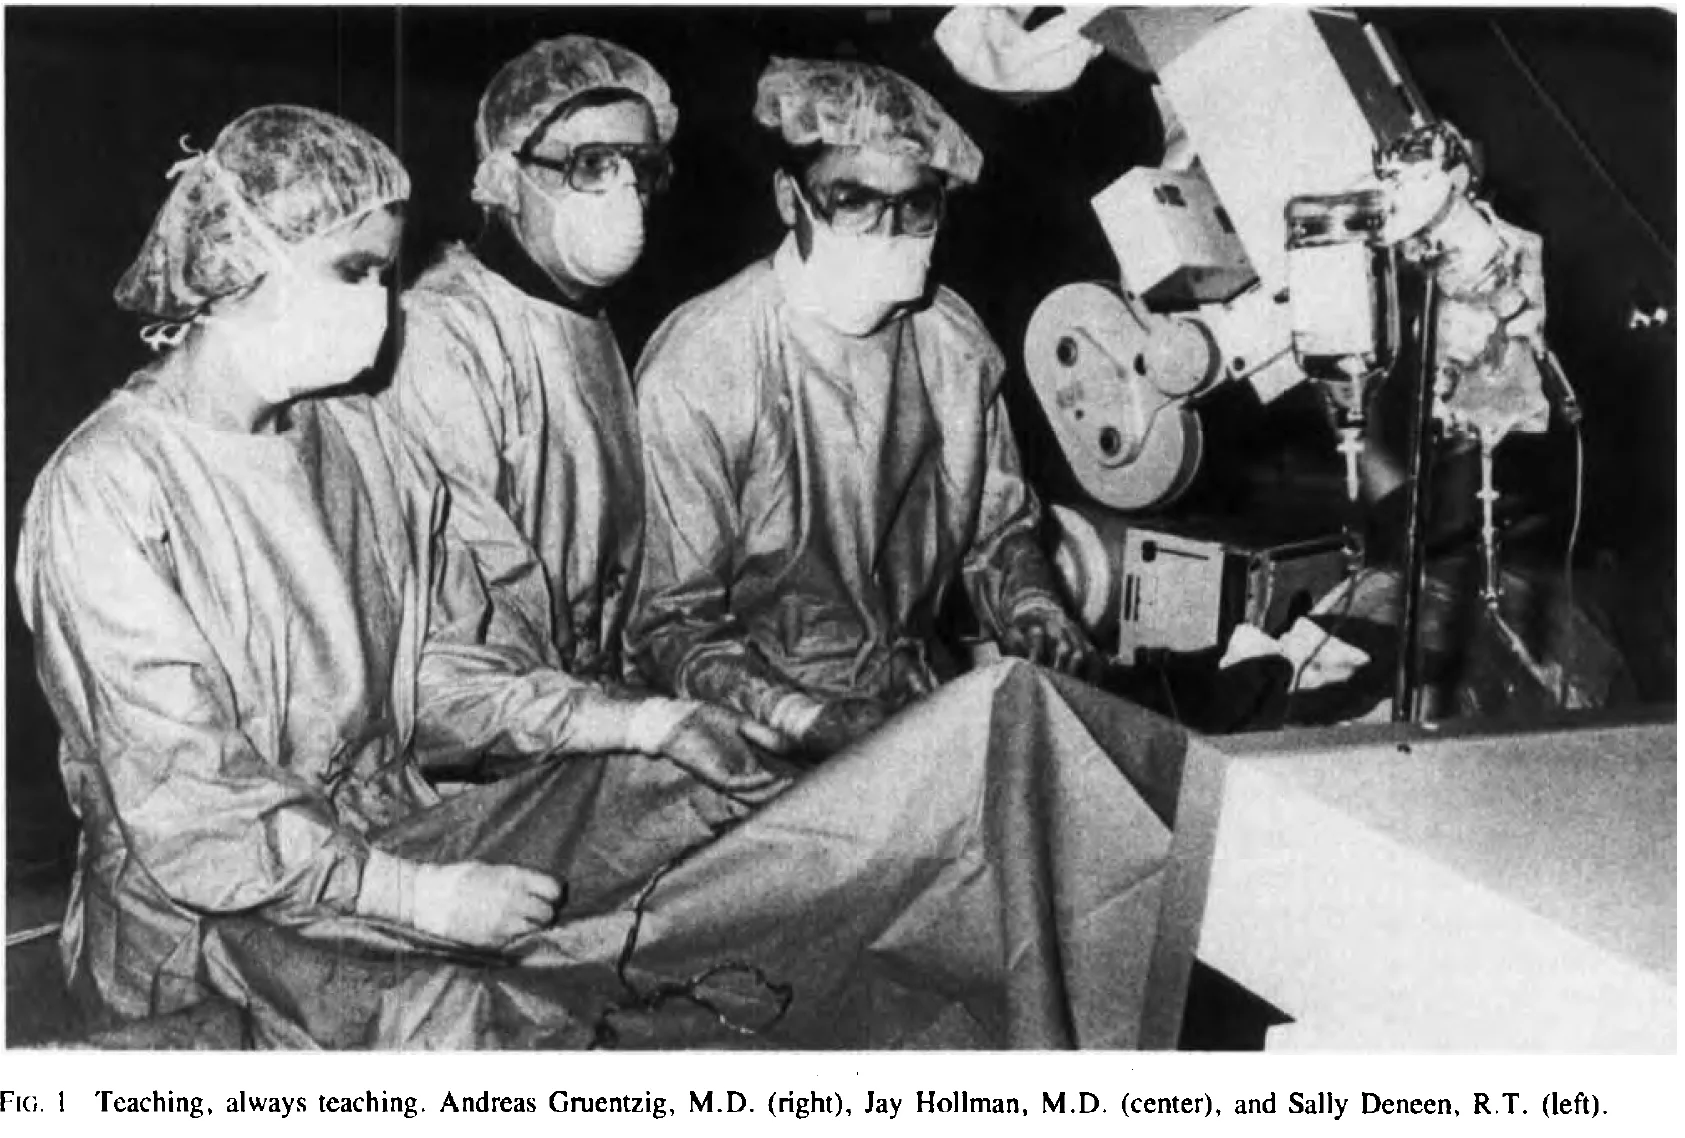

Andreas Gruentzig: The Teaching Genius - article by J. Willis Hurst

The First Balloon-Expandable Coronary Stent - An Expedition That Changed Cardiovascular Medicine - A Memoir - by Gary Roubin - 2015